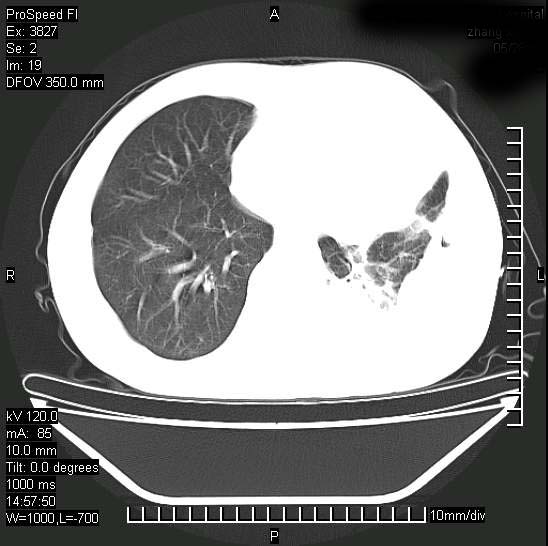

男性,一月前出现右侧肋区疼痛,较剧烈,干咳,无发热,自诉使用抗炎药后缓解,几天前又出现左侧剧烈疼痛,

发热,体温38。9,今天ct,考虑左侧包裹性脓胸,胸腔积液,右上中肺小斑片影,结核/炎症?胸水未见恶性细胞。